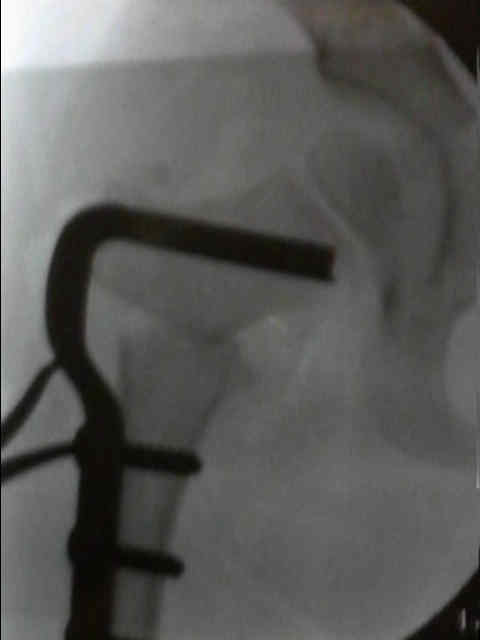

2. What is the procedure being done?

Closed reduction of a dislocated hip in a skeletally immature child with DDH, aided by arthrogram to confirm if the femoral head is concentrically reduced into the acetabulum.

- need to obtain < 5 mm constrast pooling medial to femoral head, no interposition of the limbus.

i) Reduction using Ortolani maneuvre (hip flexion and ABDuction whilst elevating the greater trochanter)

ii) +/- Adductor tenotomy (if patient has an unstable safezone, if excessive ABDuction is required to maintain reduction, so done to avoid forceful reduction)

iii) Hip spica application